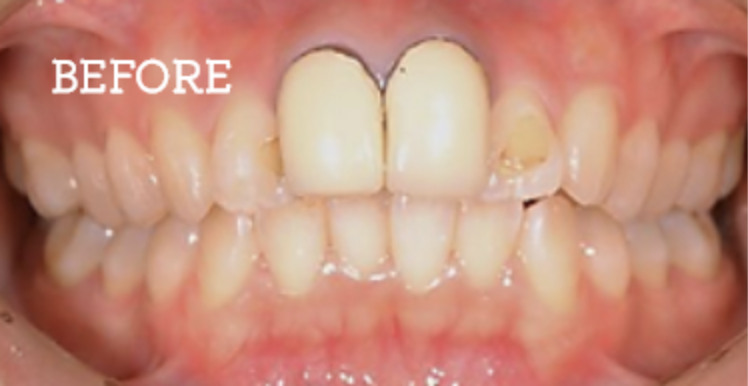

お困りごとを参考に、治療のbefore・afterが確認できます。治療過程や期間、費用などを参考にご覧ください。